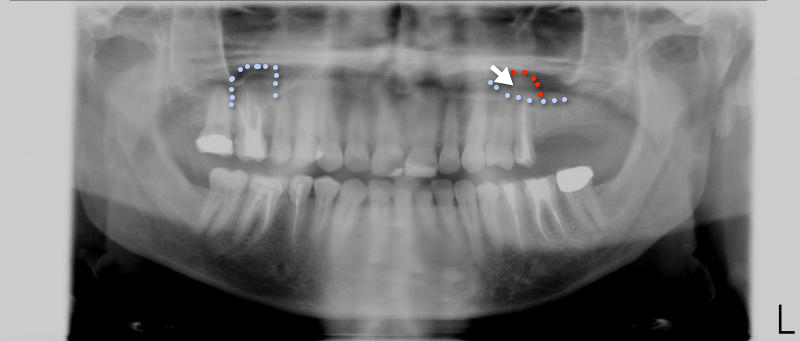

[CENTER][IMG]http://www.denta-beaute.at/forum/attachments/frage-antwort/391d1303331400-zahnschmerzen-trigeminusschmerzen-opg.jpg[/IMG][/CENTER]

linkes Oberkiefer, da ist eine Schleimhautschwellung in der Kieferhöhle, mehr dazu im Video Kieferhöhlenentzündung[/URL][/B]. Zudem glaube ich ein Fremdkörper (Pfeil). Unterkiefer links würde ich mir die Krone mittels [B][URL=”http://www.checkdent.com/de/search/bite%20wing”]Bite Wing[/URL][/B] überprüfen lassen, zudem mit einem Kleinbild den 16.

Eher überschobenes WB Material …